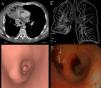

We present the case of a 56-year-old patient with a nodule in the right upper lobe (RUL) with malignant characteristics. Following right upper lobectomy, he presented frank hemoptysis and tachycardia, with persistent pulmonary opacity on X-ray. Contrast-enhanced multidetector computed tomography (MDCT) showed extensive consolidation of the middle lobe with absence of enhancement, distorted perihilar bronchi, and alteration in the normal position of pulmonary vasculature. Virtual bronchoscopy showed obliteration of the middle lobe bronchial lumen. Optical bronchoscopy revealed a compressed bronchus with a “fish mouth” appearance, which prevented introduction of the bronchoscope. Torsion and infarction of the middle lobe were suspected, and an urgent middle lobectomy was performed, which confirmed the diagnosis.